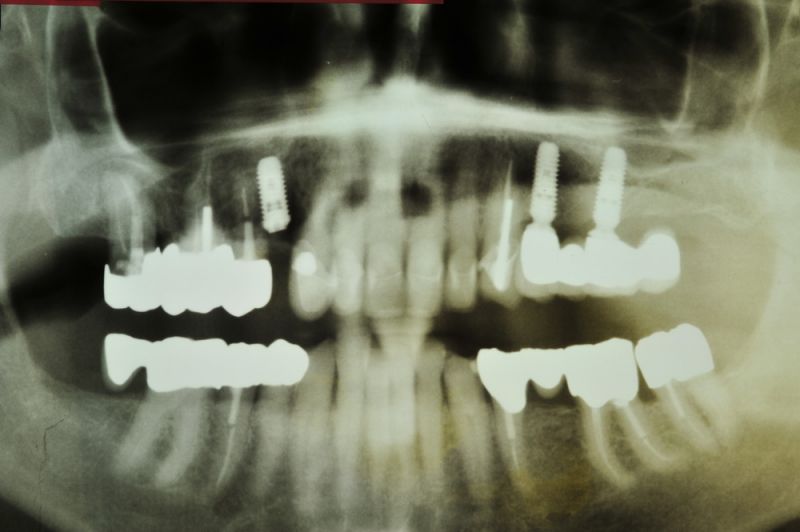

Rekonstruierter CMD Patient aus Kiel im vierteljährlichen Recall

Diese CMD Behandlungsfälle sind daher interessant, weil der Patient bereits seit 15 Jahren versorgt ist, vollkommen beschwerdefrei ist und damit deutlich wird, dass zahnärztlich funktionstherapeutischeBehandlung zwar aufwändig ist, aber eben auch sehr nachhaltig sein kann.

Das Implantat 13 ist inzwischen mit einer Einzelkrone versorgt.